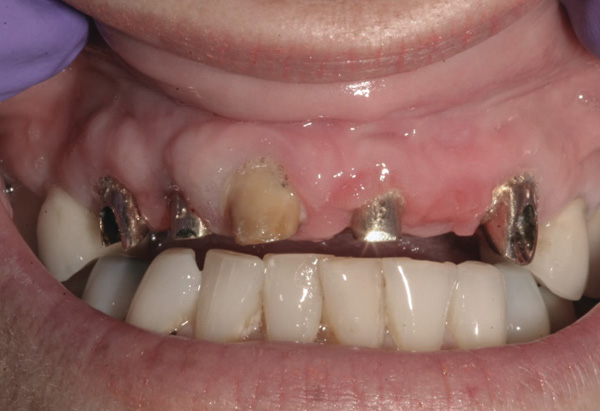

Background: The patient in this case presented with a failing dentition due to generalized severe periodontal disease with secondary endodontic lesions. She adamantly refused to wear removable transitional prostheses. Full maxillary and mandibular extractions were performed in the first phase of treatment. Not all implants could be placed in this initial phase due to the need for healing of certain grafted sites. The implants placed in this first phase were loaded with conical abutments and, in some cases, their angulated counterparts (Figure 16 and Figure 17). These stock titanium abutments were selected to avoid the need, as in Case 3, to change or remill the more costly custom abutments. They also have the advantage of making it unnecessary to use temporary cement near and around surgical sites, as they use occlusal screws only for retention.

Results: Stock titanium abutments were used until all tissue healing was achieved and the secondary implants had healed. Figure 18 shows the maxillary and mandibular custom abutments inserted. Figure 19 shows a close-up of the patient’s right side quadrants, depicting the final case 15 months after initial treatment began. Recession can be seen around units corresponding to tooth Nos. 5 and 6. In this case, the authors attempted to minimize recession susceptibility by employing stock temporary screw-retained abutments during healing phases throughout the initial stages of the treatment plan. Despite these efforts, recession still occurred in certain areas where the implants were labially placed. Since the photographs shown in this case were taken, an unsuccessful attempt was made by the patient’s surgeon to graft soft tissue around these sites with recession.

Figure 16 First-phase implants loaded with conical abutments and, in some cases, their angulated counterparts.

Figure 16

Figure 17 First-phase implants loaded with conical abutments and, in some cases, their angulated counterparts.

Figure 17